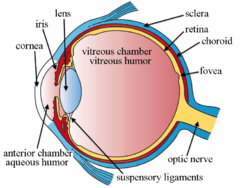

Schematic diagram of the human eye. | |

Structure

The lens is part of the anterior segment of the eye. In front of the lens is the iris, which regulates the amount of light entering into the eye. The lens is suspended in place by the suspensory ligament of the lens, a ring of fibrous tissue that attaches to the lens at its equator[1][2] and connects it to the ciliary body. Posterior to the lens is the vitreous body, which, along with the aqueous humor on the anterior surface, bathes the lens. The lens has an ellipsoid, biconvex shape. The anterior surface is less curved than the posterior. In the adult, the lens is typically circa 10 mm in diameter and has an axial length of about 4 mm, though it is important to note that the size and shape can change due to accommodation and because the lens continues to grow throughout a person's lifetime.[3]

The structures of the eye labeled

-